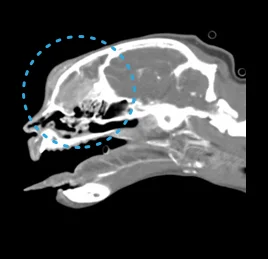

• 두경부 질환

이도의 염증, 중이염, 외이염, 두경부 종양,

갑상선 질환, 침샘류, 비강 질환, 구강 질환

• 비강 종양

• 두개골 골절